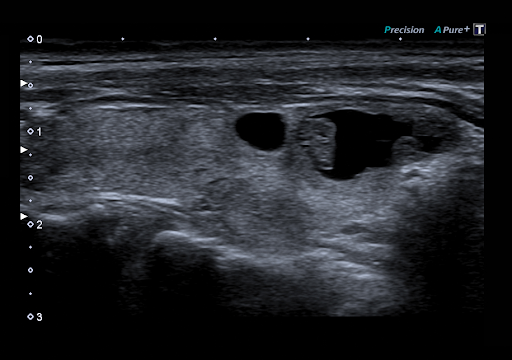

Технология Precision Imaging улучшает определение границ и делает края структур более четкими.

D-THI - Differential Tissue Harmonic Imaging - Дифференциальная тканевая гармоника

Увеличивает контрастность и пространственное разрешение на больших глубинах и у пациентов с плохой визуализацией.

Технология ApliPure+ позволяет достигать беспрецедентной однородности и детализации при сохранении клинически значимых маркеров.